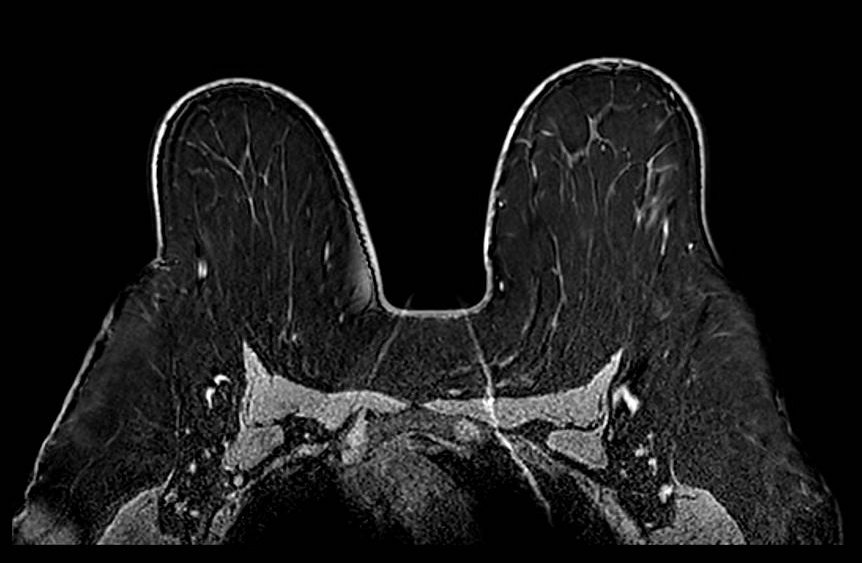

Aliasing - Axial

Aliasing (wrap-around) artifact: axial plane. Although the primary breast anatomy appears contained within the FOV, aliasing arises when anatomy outside the FOV boundary - here posterior thoracic and paraspinal soft tissues - is not adequately suppressed. Without oversampling in the phase-encode direction, these out-of-FOV signals are undersampled and fold back into the image, appearing to originate from within the breast volume. The artifact is particularly deceptive when the aliased structure is not immediately recognizable as displaced anatomy.